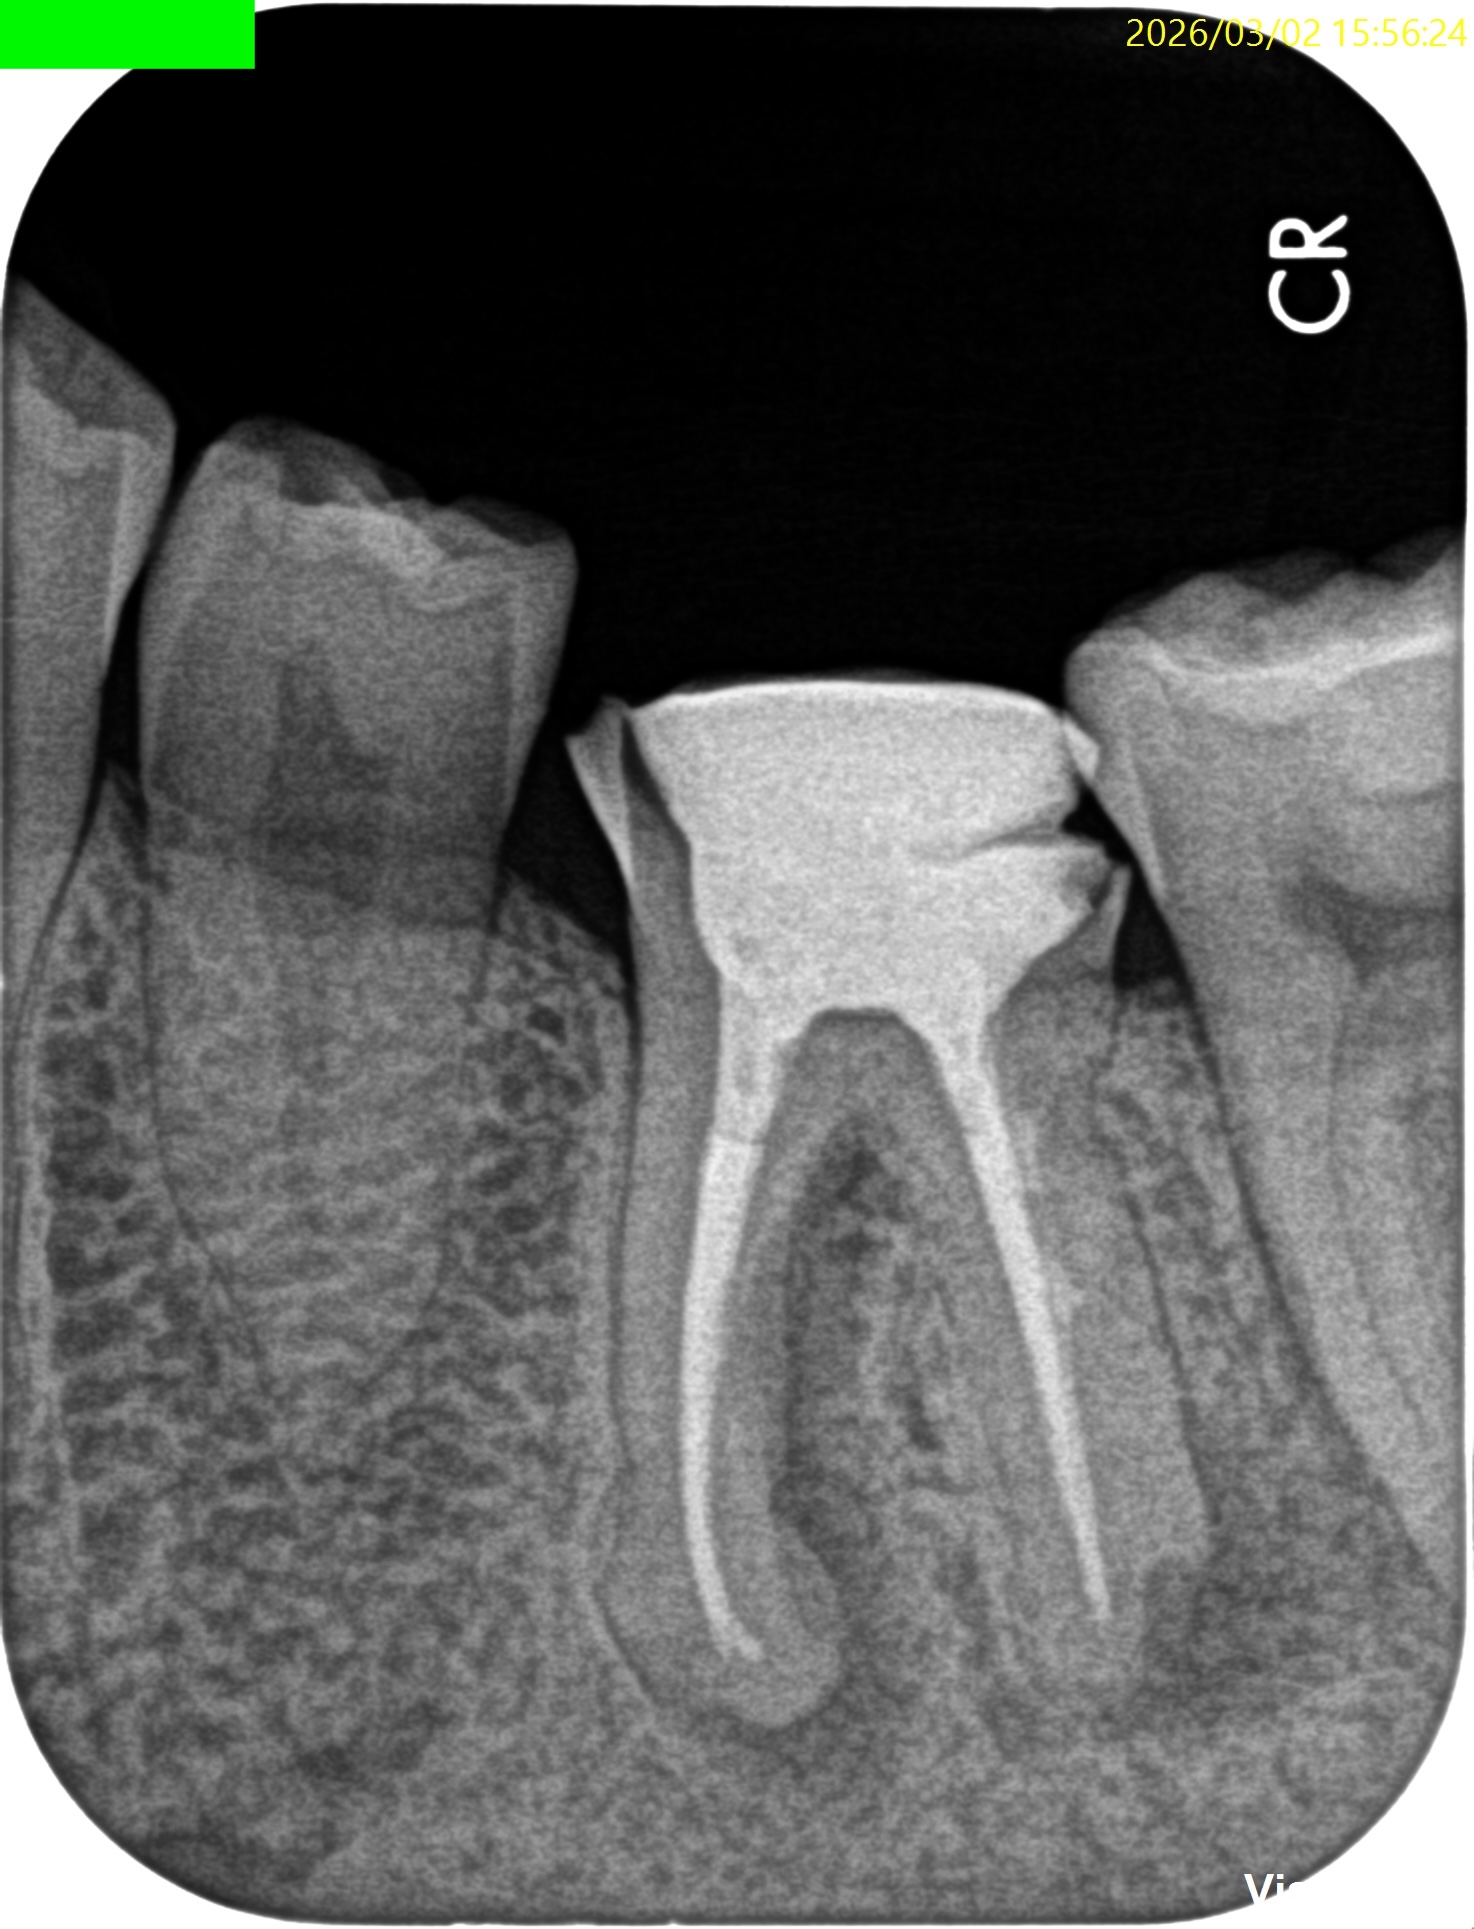

Pre-op Endo test(2026.3.2)

頬側遠心のクラウンマージン部付近にアブセスがある。

2枚のPAでは何もわからない。

MB

ML